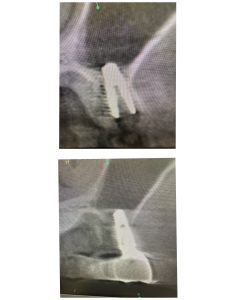

以下の画像は、本日定期検査の方

オペから9ヶ月位の画像、良いね👍👍

デンサーバーでのリフト、採血濃縮血漿板使用

異物の人工骨は一切使わない

目利きある先生方には分かるはず!